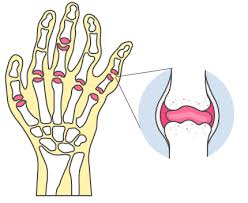

류마티스 관절염의 원인과 직접적인 영향

류마티스 관절염은 자가면역 질환으로, 면역 체계가 자신의 관절을 공격하여 염증을 유발합니다. 유전적 요인, 환경적 요인, 생활 습관 등이 복합적으로 작용하여 발생하게 됩니다. 스트레스, 흡연, 비만 등이 류마티스 관절염의 원인으로 지목되며, 특히 호르몬 변화가 증상을 악화시킬 수 있습니다. 이를 통해 류마티스 관절염은 단순한 관절 문제를 넘어 전신에 영향을 미치는 복합적인 질환임을 알 수 있습니다.